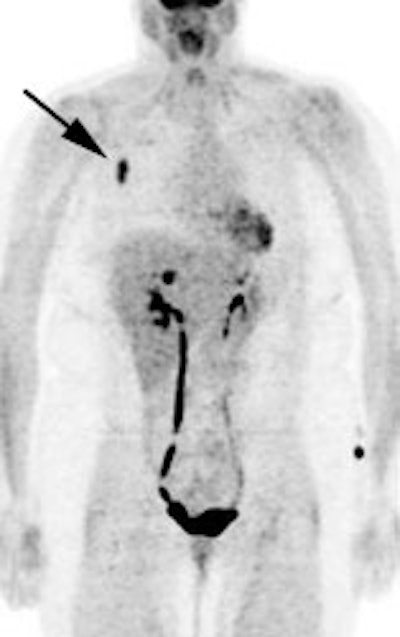

Diffuse splenic involvement: The patient shown below has non-Hodgkins lymphoma. The FDG PET exam demonstrated multiple sites of disease including diffuse involvement of the spleen, focal liver involvement, and persistent sites of adenopathy in the chest and abdomen. Case courtesy of Mercy Medical Center Alliance Imaging, Dr. Steve Allen. |

|

FDG PET imaging is more accurate than CT for the detection of lymphomatous involvement of the spleen [5,27]. On FDG PET imaging, diffuse or focal splenic uptake of greater intensity than the liver is felt to represent tumor involvement [27]. Infiltrative lymphomatous involvement of the spleen can be detected with a 67% increased frequency when compared with CT imaging [5]. Hepatic tumor involvement is characterized by focal or diffuse increased tracer accumulation [5].